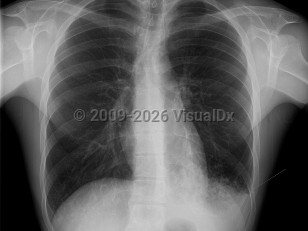

Influenza presents with classic flu-like illness consisting of the sudden onset of fever, malaise, sore throat, nonproductive cough, myalgias, headache, and nasal congestion. Chills are common, as are nausea and vomiting in children. After 48 hours, cough may increase and produce sputum. There may be associated dyspnea and/or mild-to-moderate pleuritic chest pain. Upon physical examination, unilateral or bilateral inspiratory rales may be appreciated or diminished breath sounds. Pregnant individuals are at increased risk for severe illness from influenza.

Primary viral pneumonia is the complication responsible for the most influenza-related deaths. Those with pre-existing cardiopulmonary disease or who are pregnant are at the greatest risk. The initial clinical presentation is the same, but dyspnea increases in severity. Productive cough may be blood tinged. Massive hemoptysis has been reported. When severe, there may be profound respiratory distress with tachypnea, tachycardia, and cyanosis. Rales and wheezes will spread throughout the chest from the lower lung.